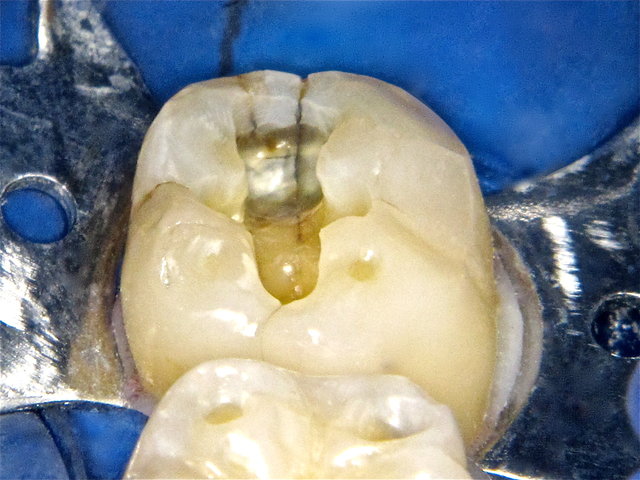

In- und externe Risse nach Amalgam-Entfernung ...

Höckerfrakturen neben Amalgam-Füllung ...

Interner zentraler Riss nach Amalgam-Entfernung ...